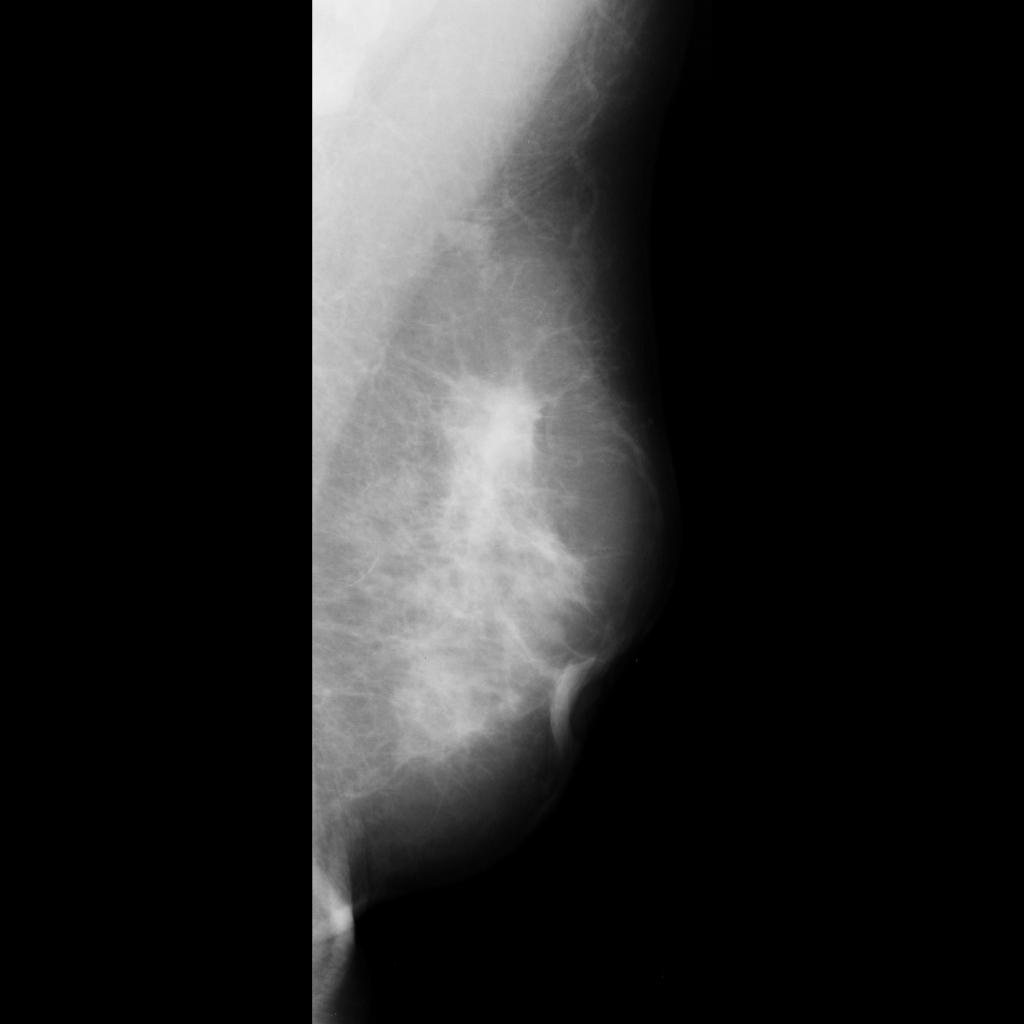

benign